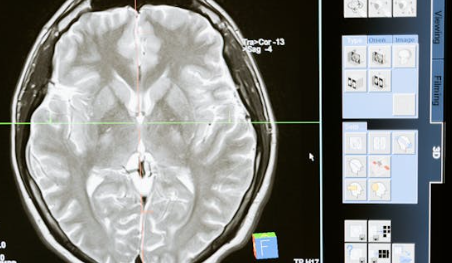

일반적인 MRI나 CT만으로는 진단이 어렵고, 다음과 같은 정밀 검사가 필요해요.

MRI & MRA로 뇌혈관 상태를 전체적으로 파악하고, 뇌혈관 조영술로 ‘연기처럼 피어나는 혈관’ 모양을 확인하며 SPECT 검사를 통해 뇌혈류 흐름을 측정해 수술 여부를 결정하게 됩니다.